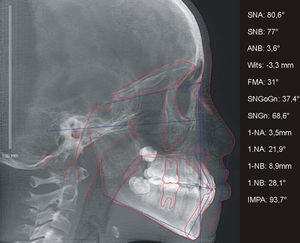

A paciente A, do sexo feminino, passou por procedimentos cirúrgicos condizentes ao protocolo de reconstrução da fenda labiopalatina na primeira infância, como queiloplastia, palatoplastia e faringoplastia12. Como esperado, houve redução da largura do arco dentário superior devido à junção dos segmentos e uma limitação no crescimento do terço médio da face. Aos 12 anos, em estágio pré‐puberal, CS1 de maturação óssea13, a paciente apresentava clinicamente um perfil côncavo, molares com padrão de oclusão em Classe I de Angle, atresia transversal maxilar severa na região anterior e mordida cruzada anterior (figs. 1 e 2). Pelo exame da telerradiografia em norma lateral da face, observou‐se a sugestão de estreitamento e constrição das vias aéreas, relação esquelética de Classe I (ANB=3,6°), mas apresentando uma tendência à Classe III (Wits=−3,3mm), maxila retroposicionada em relação à base do crânio (SNA=80,6°), bom posicionamento de incisivos superiores (1.NA=3,5mm; 1.NA=21,9°) e projeção vestibular de incisivos inferiores (1.NB=8,9mm; 1.NB=28,1°; IMPA=93,7°) (fig. 3). Como parte da documentação ortodôntica inicial para o planeamento do tratamento, que incluía os enxertos ósseos na região da fenda, a paciente foi submetido a uma tomografia computadorizada por feixes cônicos (TCFC), no tomógrafo i‐CAT (Imaging Sciences International, Hatfield, Pennsylvania, Estados Unidos da América [EUA)), com field of view (FOV) de crânio estendido (23cmx17cm), voxel de 0,3mm3, 36,90mA, 120kV e tempo de exposição de 40 segundos. Frente a todas as características encontradas, foi determinada uma maior necessidade de ERM na região anterior, em preparação para enxerto ósseo e tratamento ortodôntico corretivo. Após o diagnóstico, foi escolhido o expansor em leque. O aparelho foi confeccionado com um parafuso expansor em leque (Morelli, Sorocaba, São Paulo, Brasil). O aparelho possui bandas nos primeiros molares permanentes e uma dobradiça na região posterior, fixada em acrílico, de onde partem extensões de fio 0,9mm, apoiadas nas superfícies palatinas dos molares decíduos ou pré‐molares. Este aparelho é considerado dentomucossuportado (fig. 4).